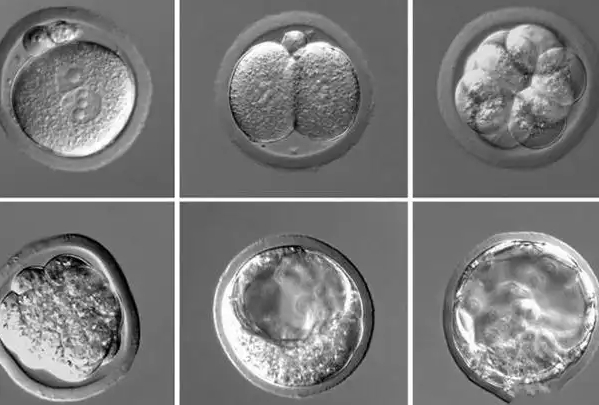

囊胚着床是循序渐进的生理过程,主要分为三个核心阶段。第一阶段是定位,移植后的囊胚会在子宫腔内缓慢游离,寻找子宫内膜容受性最佳的区域;第二阶段是黏附,囊胚找到合适位置后,会与子宫内膜表面的受体结合,逐渐黏附在子宫内膜上;第三阶段是侵入,囊胚会突破子宫内膜上皮细胞,侵入到子宫内膜基质中,完成“扎根”。整个过程需要精密配合,通常从移植后开始,持续6-12天左右才能完成,不存在快速完成的可能。

临床数据显示,多数囊胚会在移植后3-7天内启动着床过程,部分囊胚可能因自身发育情况、子宫环境等因素,着床时间会稍晚,一般不超过12天。移植后前1-2天,囊胚主要处于子宫内游离状态,并不会立即着床;直到移植3天后,部分优质囊胚才会开始黏附、侵入,逐渐完成着床。因此,移植后短期内无需过度关注是否着床,耐心等待才是关键。